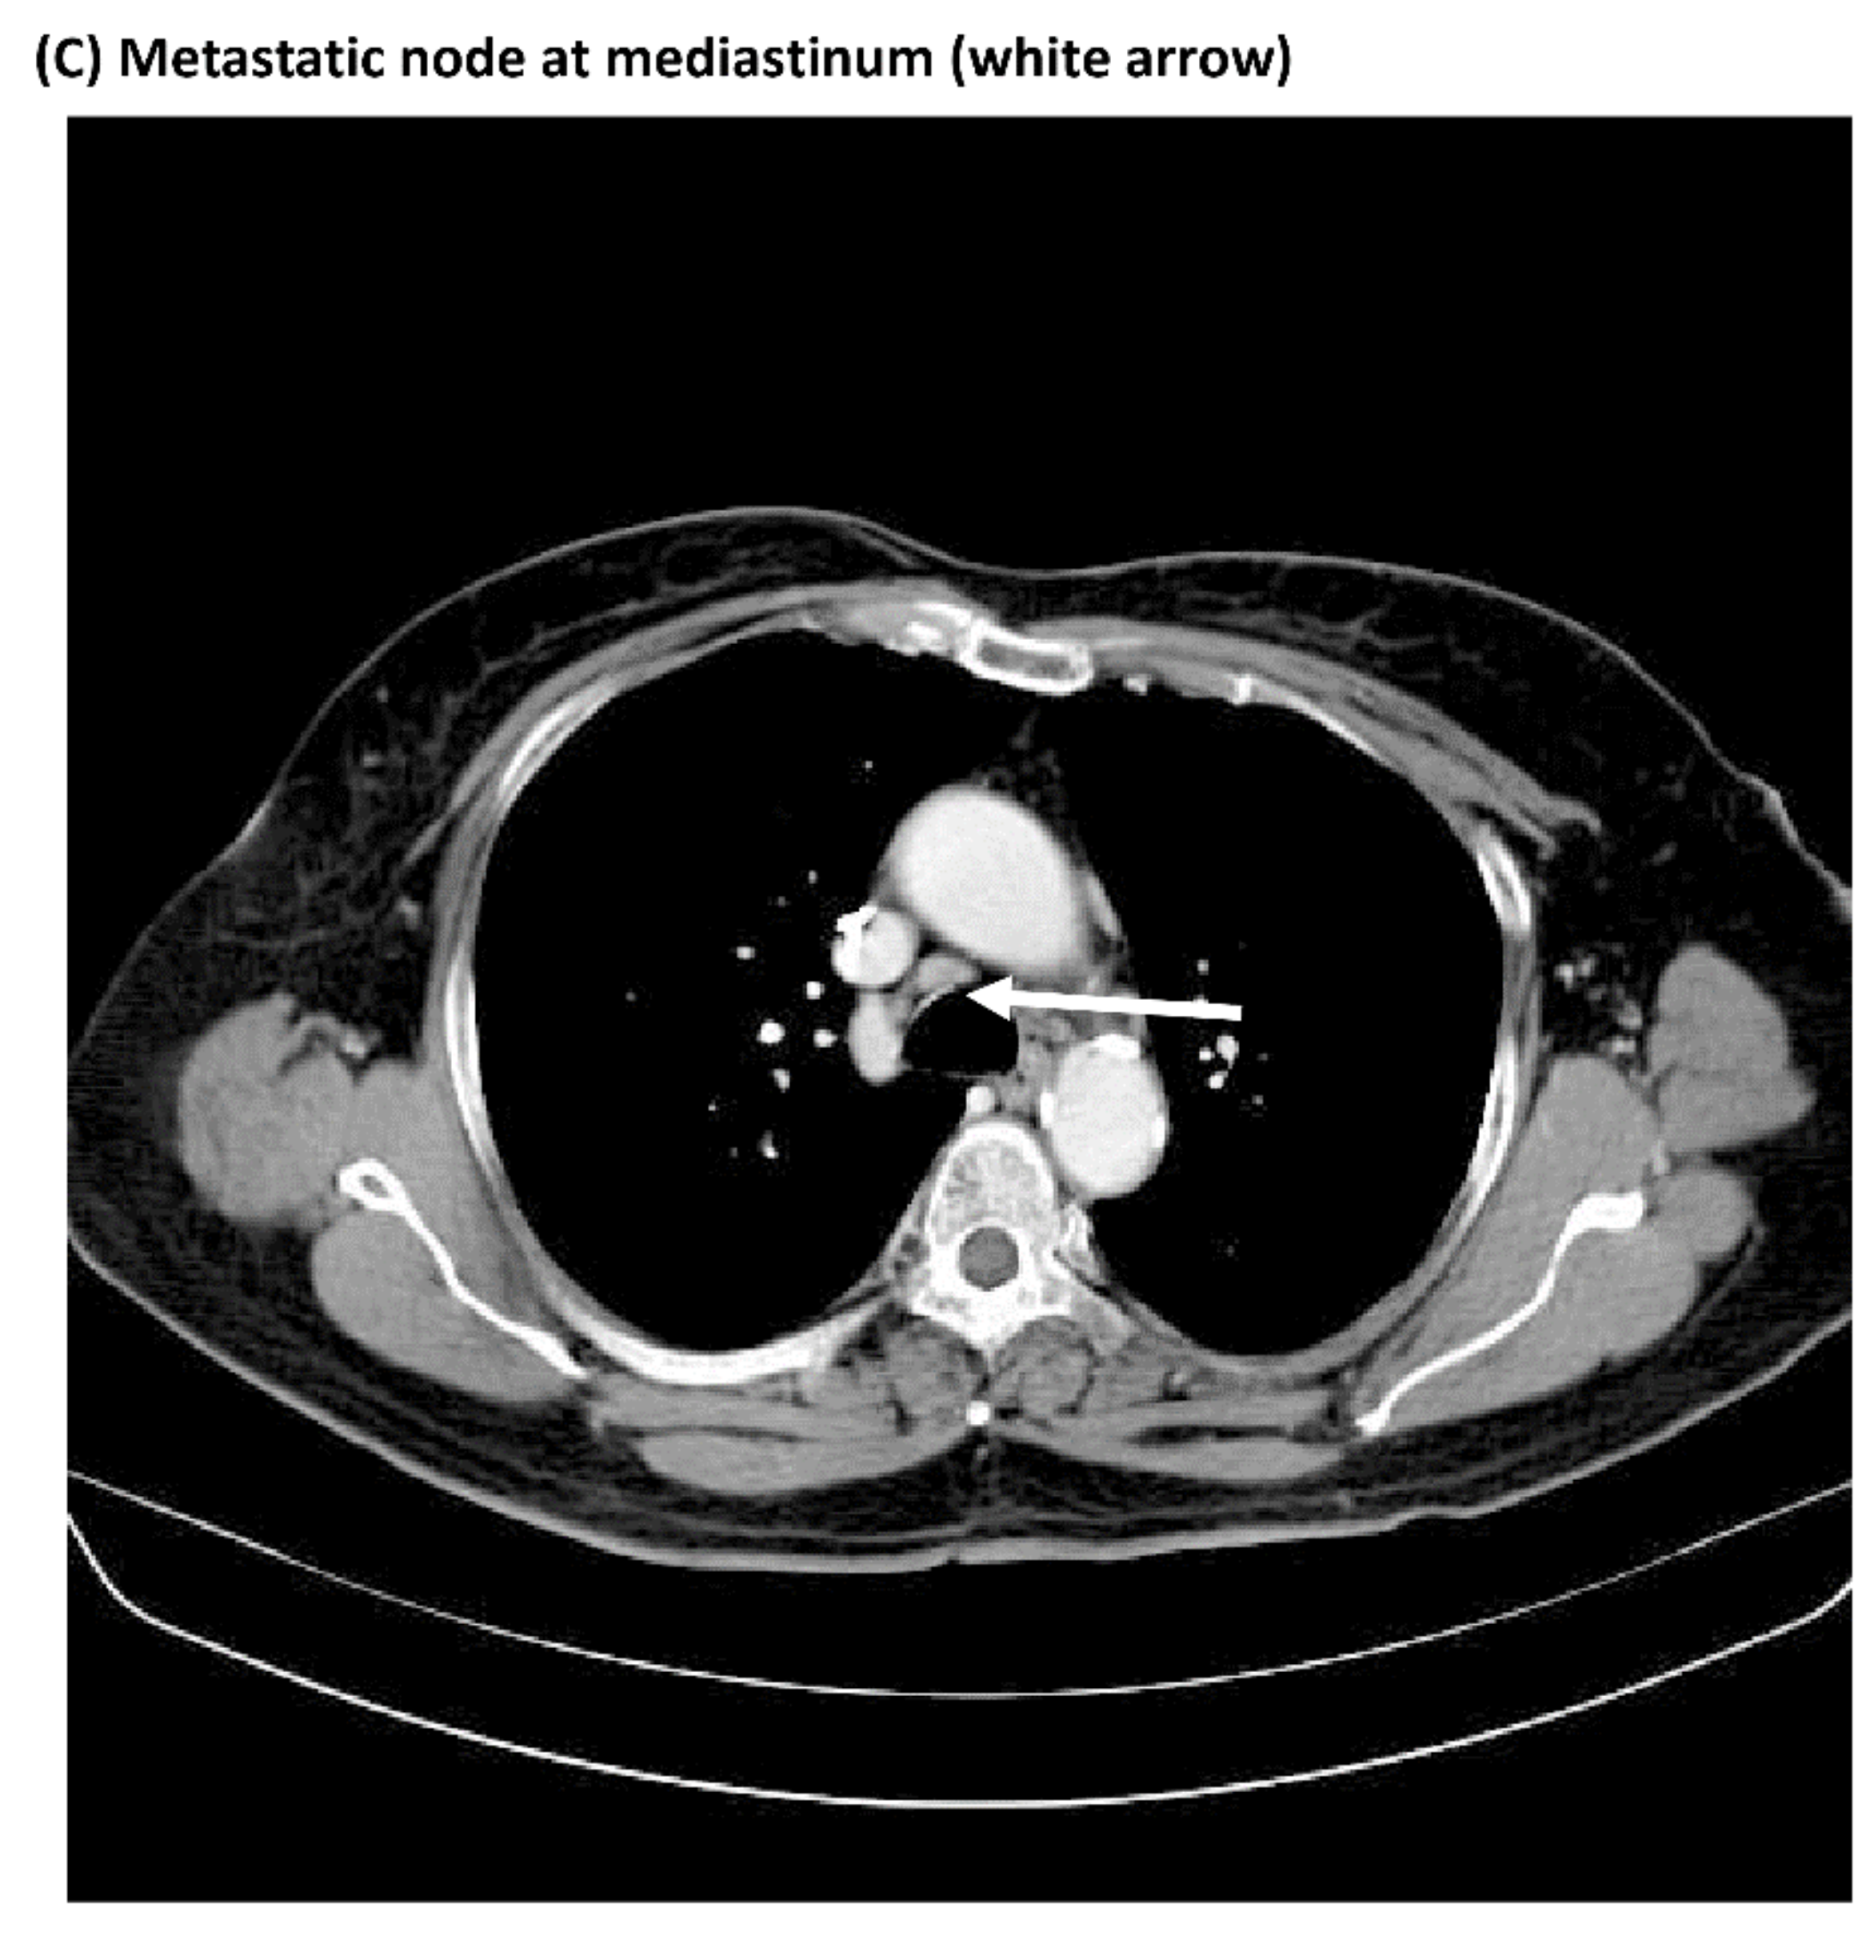

3.3. Comparisons of Immunostaining of NFκB between Pre-Treatment Samples and Recurrent Samples